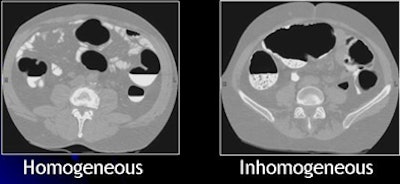

| Images show CTC data before and after electronic cleansing. All images courtesy of Hiro Yoshida, Ph.D. |

The general assumptions in EC development are that residual feces are fluid rather than solid, that tagging is homogeneous, and that bowel cleaning is rigorous, Yoshida said. But the reality is quite different. CTC exams come with widely divergent levels of quality in tagging and cleansing. A wide variety of bowel preparation techniques and agents are emerging for use in CTC, he said.

| Inhomogeneous tagging often appears in reduced or nonlaxative CTC. The uneven appearance of tagged materials on CTC data represents a mixture of semisolid fecal materials, air bubbles, fat, undigested foodstuffs, and unevenly distributed contrast agents. |

Inhomogeneous tagging often appears in reduced or nonlaxative CTC data, resulting from a mixture of semisolid fecal materials, air bubbles, fat, undigested foodstuffs, and unevenly distributed contrast agents.